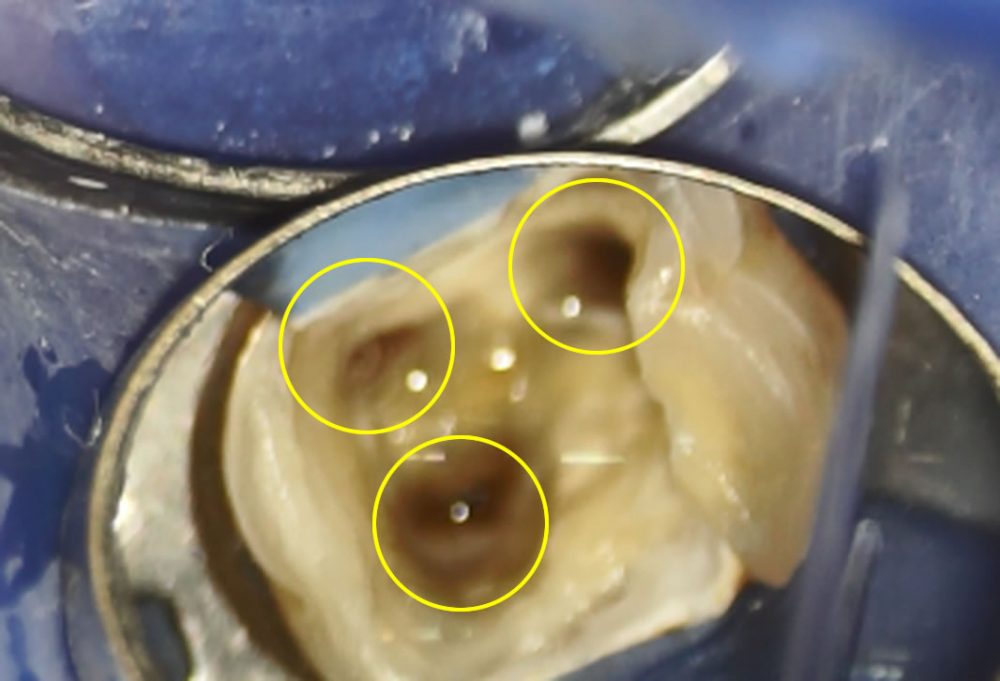

マイクロスコープを用いた精密根管治療の実施

マイクロスコープで視野を拡大して虫歯部分をすべて取った後、根の消毒を始めます。今回の歯は術前にCTで根の入り口が3つあることがわかっています。

根管内の消毒